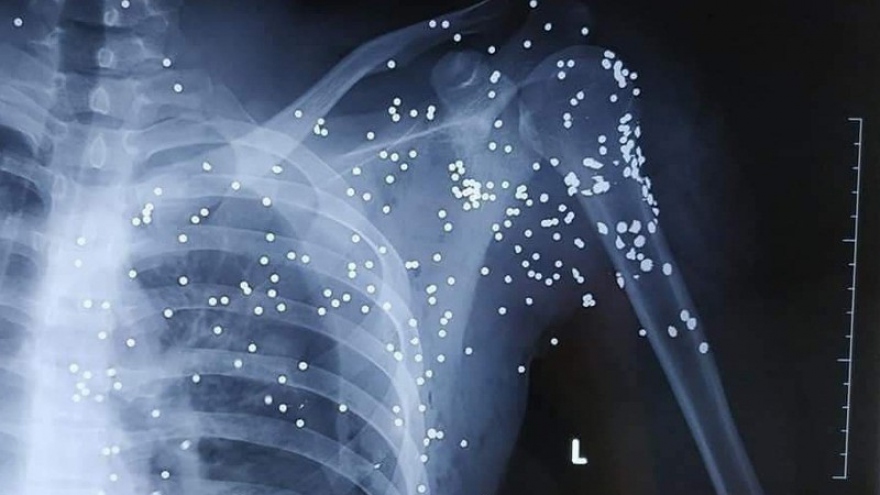

VOV.VN - Vụ nổ súng tại quán karaoke X.O ở Tiền Giang khiến 1 người chết, 3 người bị trọng thương.

VOV.VN - Sáng 17/3, Viện kiểm sát nhân dân tỉnh Tiền Giang cho biết, các cơ quan chức năng đang phối hợp điều tra, làm rõ nguyên nhân dẫn đến vụ dùng súng thanh toán nhau làm 3 người thương vong.